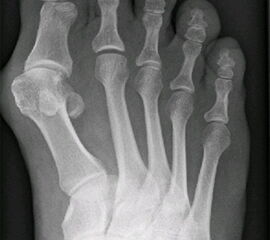

Abbildung 1

Nach Anamneseerhebung stellen die klinische Untersuchung und die Durchführung von belasteten Röntgenaufnahmen in zwei Ebenen die wesentlichen Pfeiler für die spätere Operationsplanung dar. Bei der Inspektion können Begleitpathologien detektiert werden wie z.B. plantare Schwielenbildung unter dem Metatarsale-II-Köpfchen

(Abb. 1) als Ausdruck einer Überlastung des 2. Strahles oder aber Schwielenbildungen im Bereich der Beere der Großzehe bei Torsionsfehlstellungen und eingeschränkter Beweglichkeit des Großzehengrundgelenkes. Die typische Fehlstellung der Großzehe selbst im Sinne eines Hallux valgus interphalangeus am Grundglied ist ebenfalls oft nachzu weisen. Im Falle einer Rigiduskomponente liegt die knöcherne Prominenz am Köpfchen des 1. Mittelfußknochens eher dorsalseitig. Bei der Palpation können spezifische Schmerzpunkte gefunden werden. Bei der Beweglichkeitsprüfung deuten Einschränkungen der normalen Dorsalextension von 70-90° passiv auf beginnende arthrotische Veränderungen hin, die Beweglichkeitsprüfung des Endgelenkes dient zum Ausschluss von degenerativen Veränderungen auch in diesem Gelenk. Für die Wahl des Operationsverfahrens entscheidend ist die im Video beschriebene Stabilitätsprüfung: Um dem funktionellen Aspekt der stabilisierenden Muskulatur Rechnung zu tragen, prüfen wir bei der klinischen Untersuchung die Mobilität des 1. Strahles, durch Testen der relativen Beweglichkeit des Metatarsale I gegenüber den kleineren Metatarsalia, einmal im entspannten Zustand und anschließend nachdem der Patient aktiv die Peronealmuskulatur durch Anheben des lateralen Fußrandes angespannt hat (Abb. 2 u. Abb. 3) (Video 1).